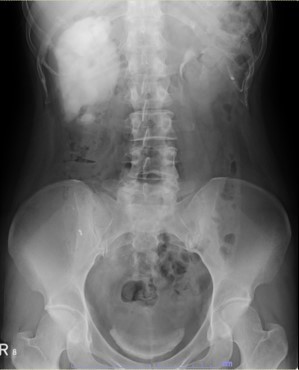

水腎症

水腎症とは、腎臓で産生された尿が通る経路(尿路:腎盂、尿管、膀胱、尿道)に生じた何らかの通過障、または膀胱の尿が腎臓側へ逆流することによって発生する腎臓(腎盂)の形態的な異常で、腹痛または腰痛、感染症(腎盂腎炎、膿腎症)や腎機能の低下などの原因となります。水腎症は、尿路結石、排尿障害(前立腺肥大症、神経因性膀胱など)、腫瘍(尿路、消化管、婦人科)、先天性疾患(尿路奇形)などによって起こります。

診断は超音波検査で行い、水腎症の程度を含めた評価が可能です。重度の水腎症や他の疾患の関与が考えられる場合は、考えられる原因に合わせて血液検査や内視鏡検査(膀胱鏡検査)、CT検査でさらに精査します。腎盂、尿管に発生した疾患が疑われる場合では、麻酔の上で逆行性尿路造影検査や内視鏡検査(尿管鏡検査)を行い、その原因を特定します。また膀胱尿管逆流症の診断では、排泄時尿路造影検査を行い、逆流の有無を評価します。